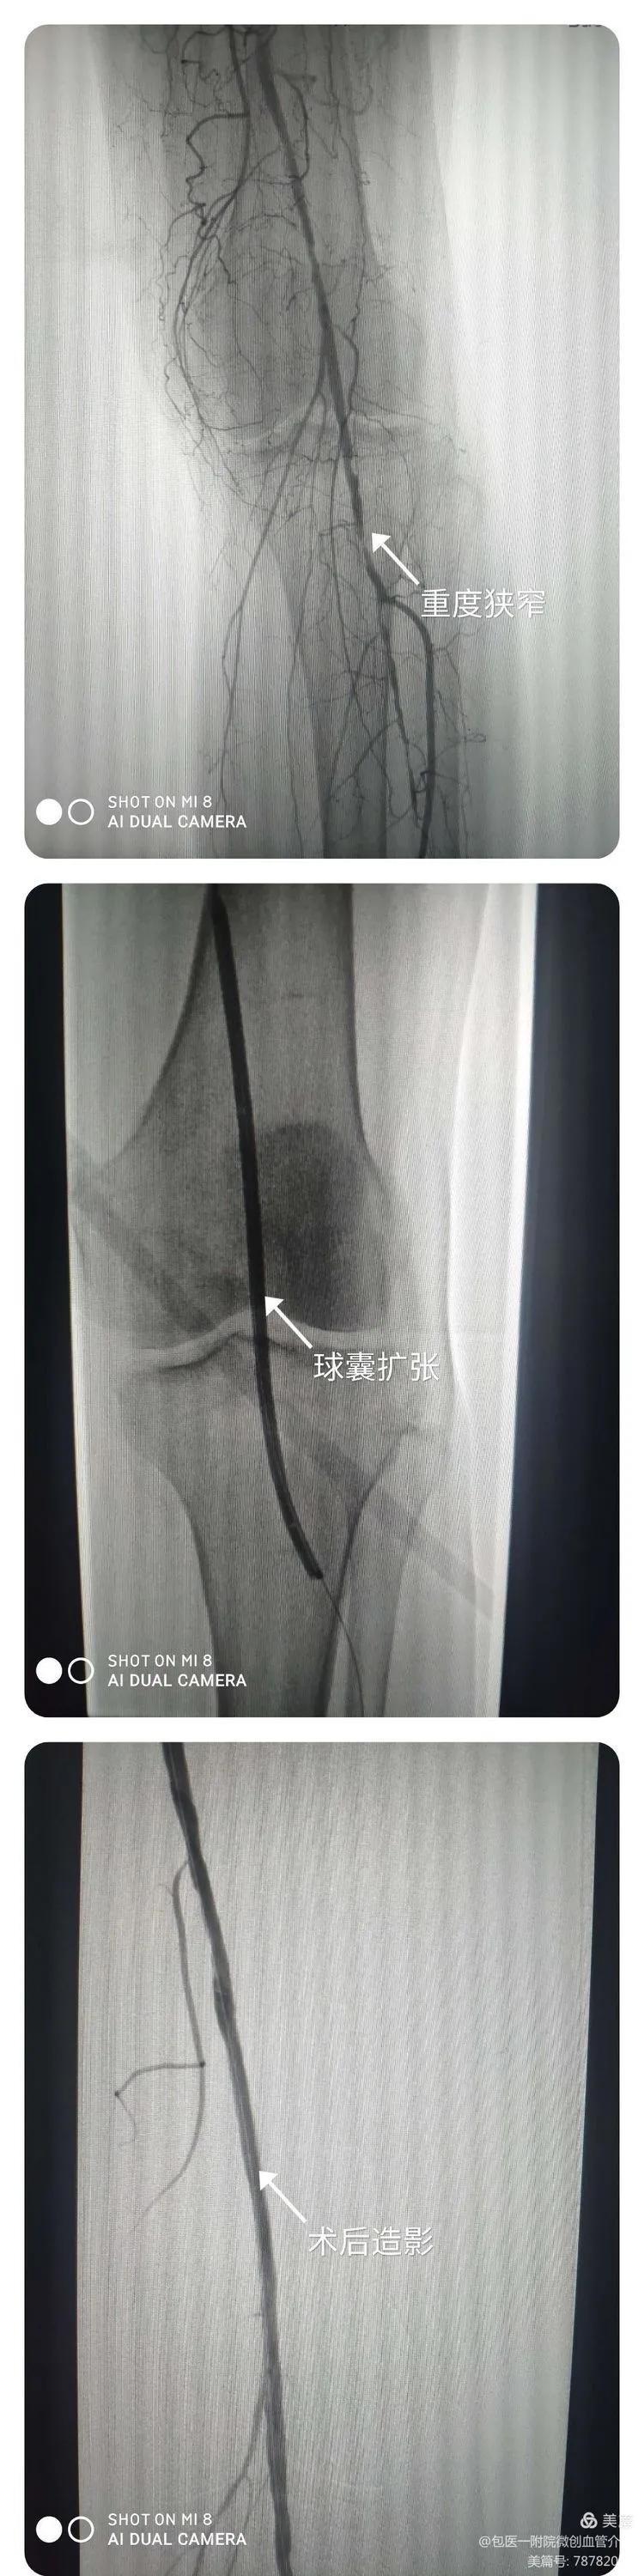

下肢动脉重度狭窄介入治疗术

患者间歇性跛行并伴随下肢疼痛2年有余,术前最远行走距离200米,术后患者下肢疼痛消失,皮温恢复正常,可正常行走。